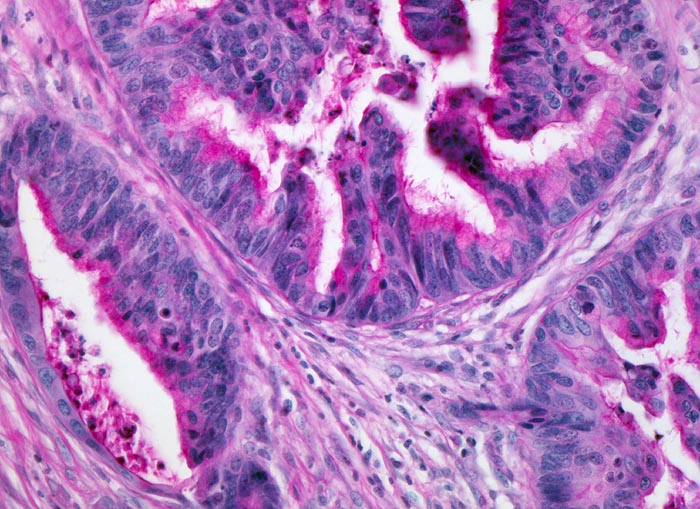

Morphologie:

Die meisten Adenokarzinome des Kolons bilden Drüsen. Die Drüsenlumina enthalten oft nekrotischen Detritus und variable Mengen von Schleim. Der intraluminale nekrotische Detritus findet sich oft auch in den Metastasen kolorektaler Karzinome und gibt einen morphologischen Hinweis auf die Lokalisation des Primärtumors, wenn nur Gewebe aus einer Metastase für die histologische Untersuchung zur Verfügung steht.

Das Tumorgrading basiert auf dem Ausmass der Drüsenbildung (>50% Drüsenbildung = low grade, <50% Drüsenbildung = high grade).

Prognostisch ungünstige histologische Parameter sind Lymphgefäss- und Veneninvasion, Perineuralscheideninvasion, hohes Tumorbudding (zahlreiche kleine Tumorzellcluster im Bereich der Tumorinvasionsfront) und Nachweis von Tumorgewebe im Resektionsrand.